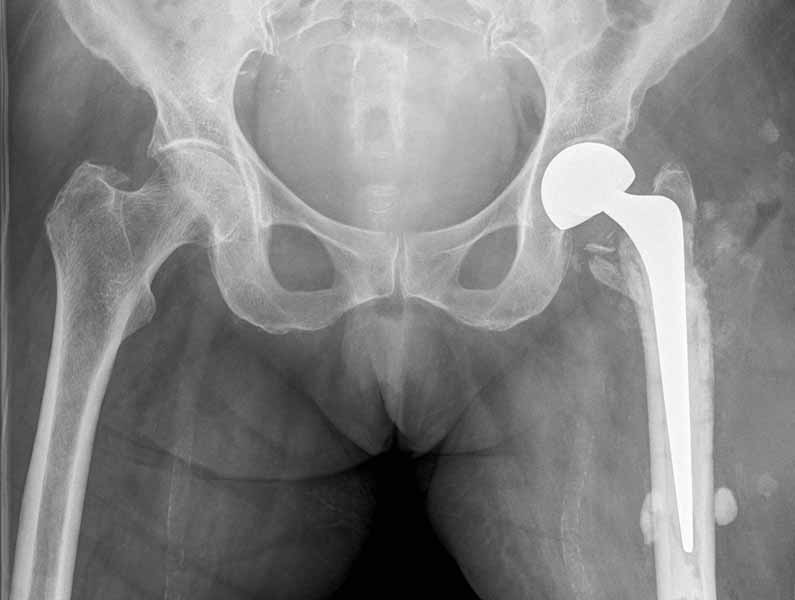

Сеньоры-пэры ревизировали гвоздем, шуруп поставили по той же дорожке, только поглубже. Да еще и bone graft не пожалели. "Результат" уже был через 2 дня.

Если сохранять головку - думаю надо было в валгусе фиксировать перелом гвоздем, или DCS, т.к. все-равно разрезали, чтоб достать DHS.

Бедная бабушка!

Неужели фиксация протеза бесцементная? Да и чашка не запрессована как надо.Грустно(

Эт -ж биполяр:)) Ножка цементная. Страйкеровский Exeter.1

биполярный эндопротез все же не лучший выбор для данной ситуации.судя по снимкам мышечные прикрепления на вертелах утрачены.Возможно здесь подошла бы более стабильная конструкция.Ваше мнение?

Constrained Acetabular Liners???

Biomet RingLoc® II

Что еще можно найти?

Наверное как раз какой-то из "связанных" эндопротезов при потере мышечных креплений будет здесь уместнее.

а куда делся фрагмент большого вертела? Очевидно,

Если среднеягодичная мышца не рефиксирована, то ничто не держит протез во впадине и это закономерный результат.

Третья операция-продолжения усилии “синьорами пэрами” по разрушению нормальной анатомии. Крест на головку! По видимому возраст позволяет биполярную конструкции, и при дефекте calcar пошли на обычный цементный. Ягодичные мышцы потеряли связь с вертелом, т.е. отсутствует верхний удержатель, и результат “a Big Screw Up!” Снимки вызывают головокружение!

Если хирурги не устали от своих “творчеств”, тогда можно ре-оперировать с calcar replacement stem, и собрать остаток ягодичных мышц. Глубина и отстутствие артроза позволяет применить любой, биполярный или тотальный, хотя принять решение можно после ревизии ацетабулума.